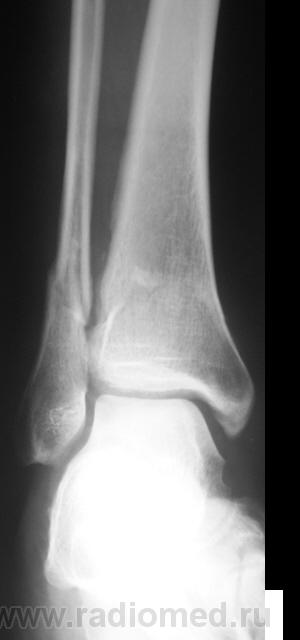

Травма. Перелом. Произведена рентгенография в стандартных проекциях в ургентном порядке.

Внутрисуставной перелом заднего края дист.эпиметафиза б/б кости или перелом "третьей лодыжки", со смещением фрагмента по ширине кзади,по длине - кверху до 5 мм и под углом, открытым кзади, с подвывихом стопы кзади, оскольчатый перелом н/3 диафиза м/б кости со смещением дистального фрагмента по ширине, по длине и угловым /открытым кзади/.

ну и еще перелом внутренней лодыжки